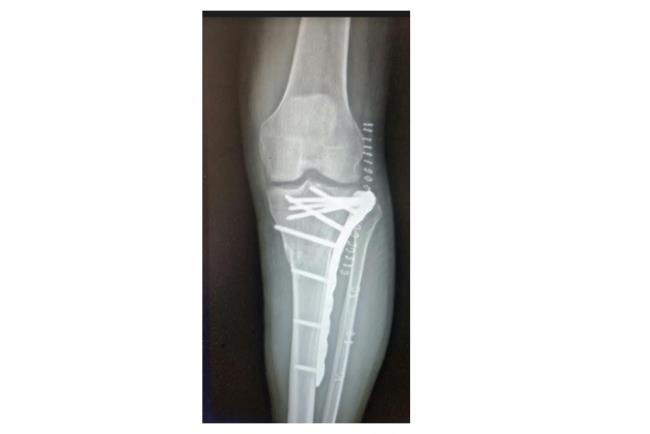

הניתוחים לאיחוי שברים מורכבים מתבצעים בשני שלבים: בשלב הראשון אם קיימות פציעות מורכבות או טראומה קשה מאוד, נפנה לטיפולים מצילי חיים. כמו כן, טרם ביצוע הניתוח יש לבחון אם קיימות פגיעות ברקמות רכות, העצבים או כלי הדם הסובבים את העצם הפגועה. הניתוח עצמו כולל כאמור חיבור של חלקי העצם באמצעות לוחות וברגים לשם יצירת מפרק חדש. בסיום הפעולה יש לוודא שהמפרק יציב. יציבות הקיבוע חשובה על מנת למנוע קיבוע של האזור לאחר ביצוע הפעולה. בצורה זו אנו מאפשריםהפעלה מיידית של המפרק, ומבטיחיםתוצאה טובה יותר שלטווחי תנועה בעתיד.

קיבוע של שבר במרפק והחלפת ראש רדיוס | באדיבות פרופ' דורון נורמן